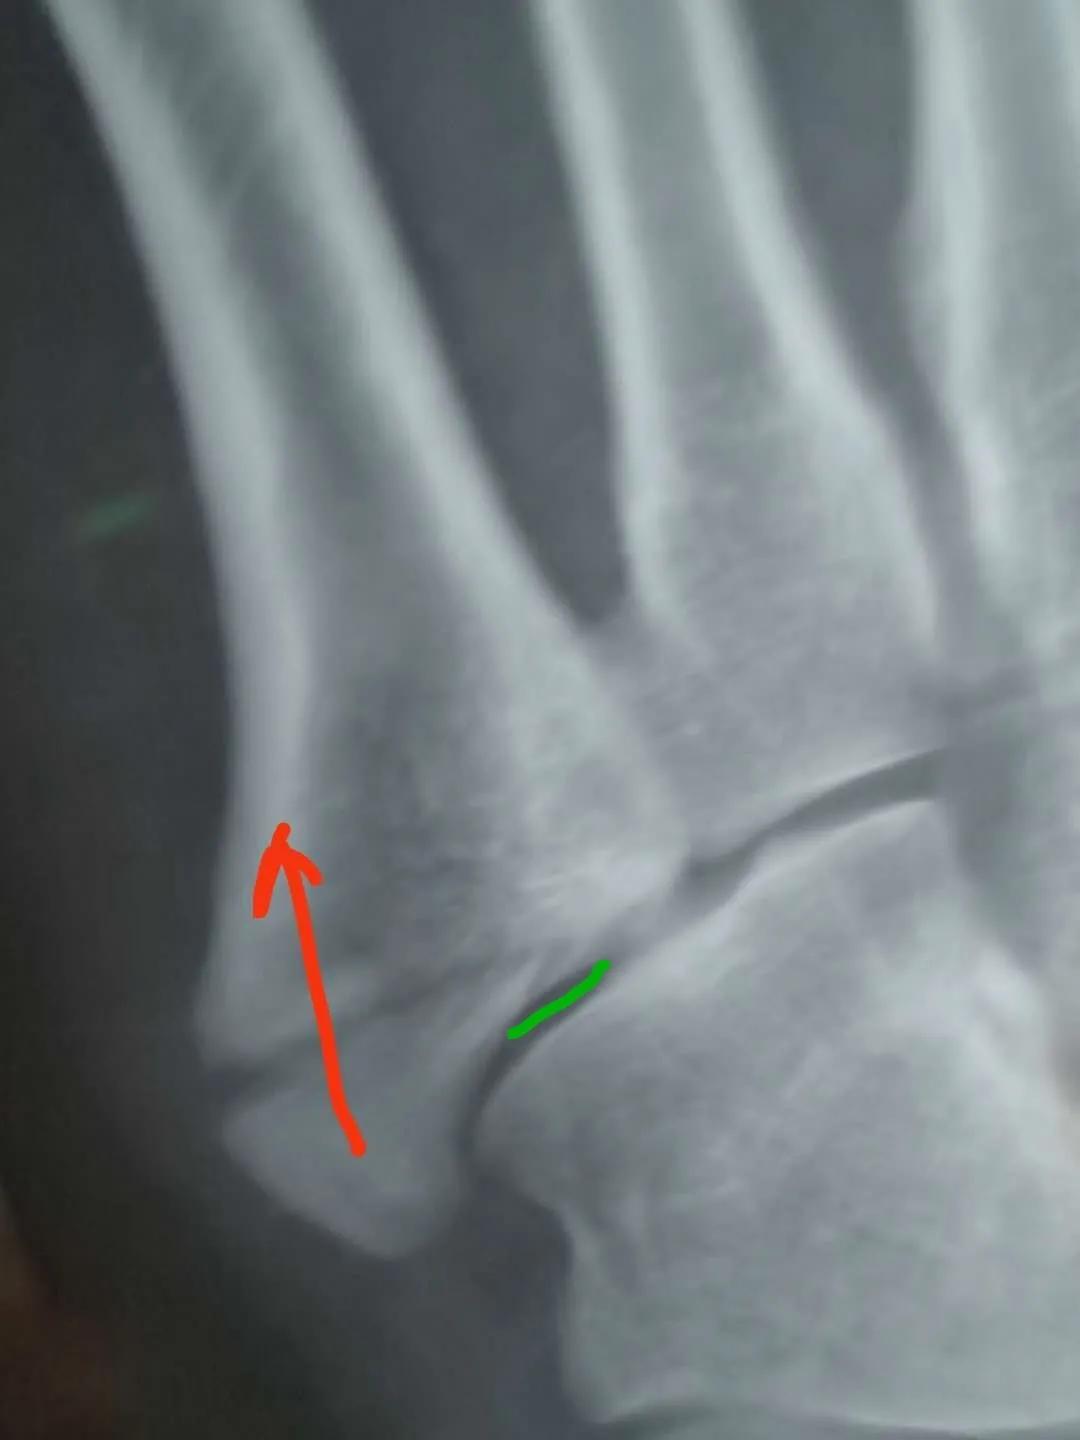

6月底复查,骨缝小的地方已经有了一点愈合的痕迹,医生说如果手术可以在红线位置打个钉子,但是现在打会破坏内部已经开始愈合的部分,建议继续保守……

按照此文意见其实已经具备手术指征